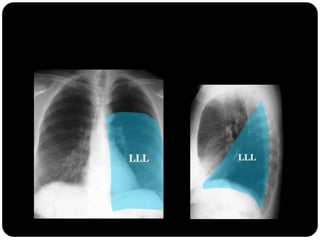

inferior esquerdo

Atelectasias de lobos

inferiores deslocam

o hilo posterior e

medialmente;

Atelectasia do LIE

 Atelectasia LIE:

 Opacidade triangular na área retrocardíaca

em incidência frontal;

 Fissura oblíqua deslocada mais

posteriormente e rodada em orientação

mais sagital do que a orientação coronal

normal;